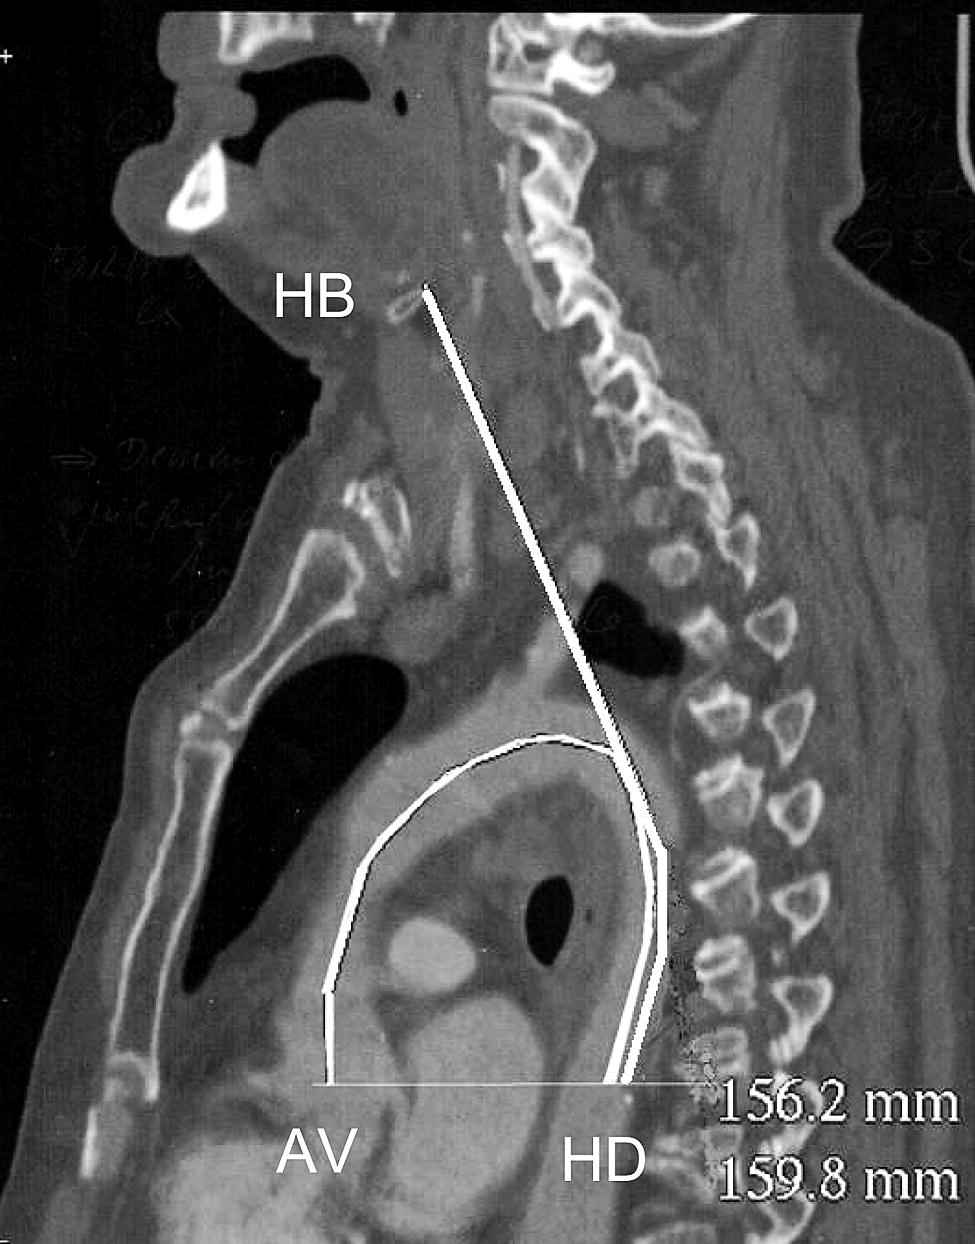

Measurements on the CT scans were performed by a trained radiologist. The examinations were performed in patients referred to the radiology department of Redon hospital between March and April 2009 for a standard chest CT scan, regardless of their primary pathology. Patients were in supine resting position during the examination. MultiPlan Reconstruction oblique scan views were made after identification of the aortic valves (AV) in the horizontal section. The aortic arch was measured from the aortic valves (AV) to the intersection with the horizontal line passing through the aortic valves and the thoracic descending aorta (HD - Fig. 1). From this latest point (HD), we measured the distance to the hyoid bone (HD-HB).

Measurement in semicircle of the aortic arch (AV-HD) = 156.2 mm, and 159.8 mm distance to the hyoid bone (HD-HB).